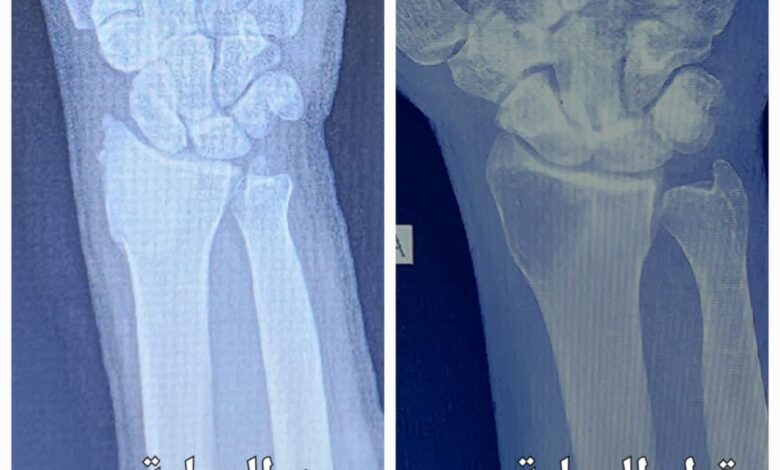

وأوضحت إدارة المستشفى أن الفحوصات الشعاعية والرنين المغناطيسي أظهرت وجود ورم عظمي مع تآكل في أسفل عظم الكعبرة. وبعد استكمال جميع التحضيرات الطبية واستشارة طبيب التخدير، أُجريت العملية التي تكللت بالنجاح التام. وشملت العملية رفع الورم، وجرف باطن الرسغ، وكي جدار الورم، ووضع عجينة إسمنتية عظمية، مع الحفاظ الكامل على المفصل.